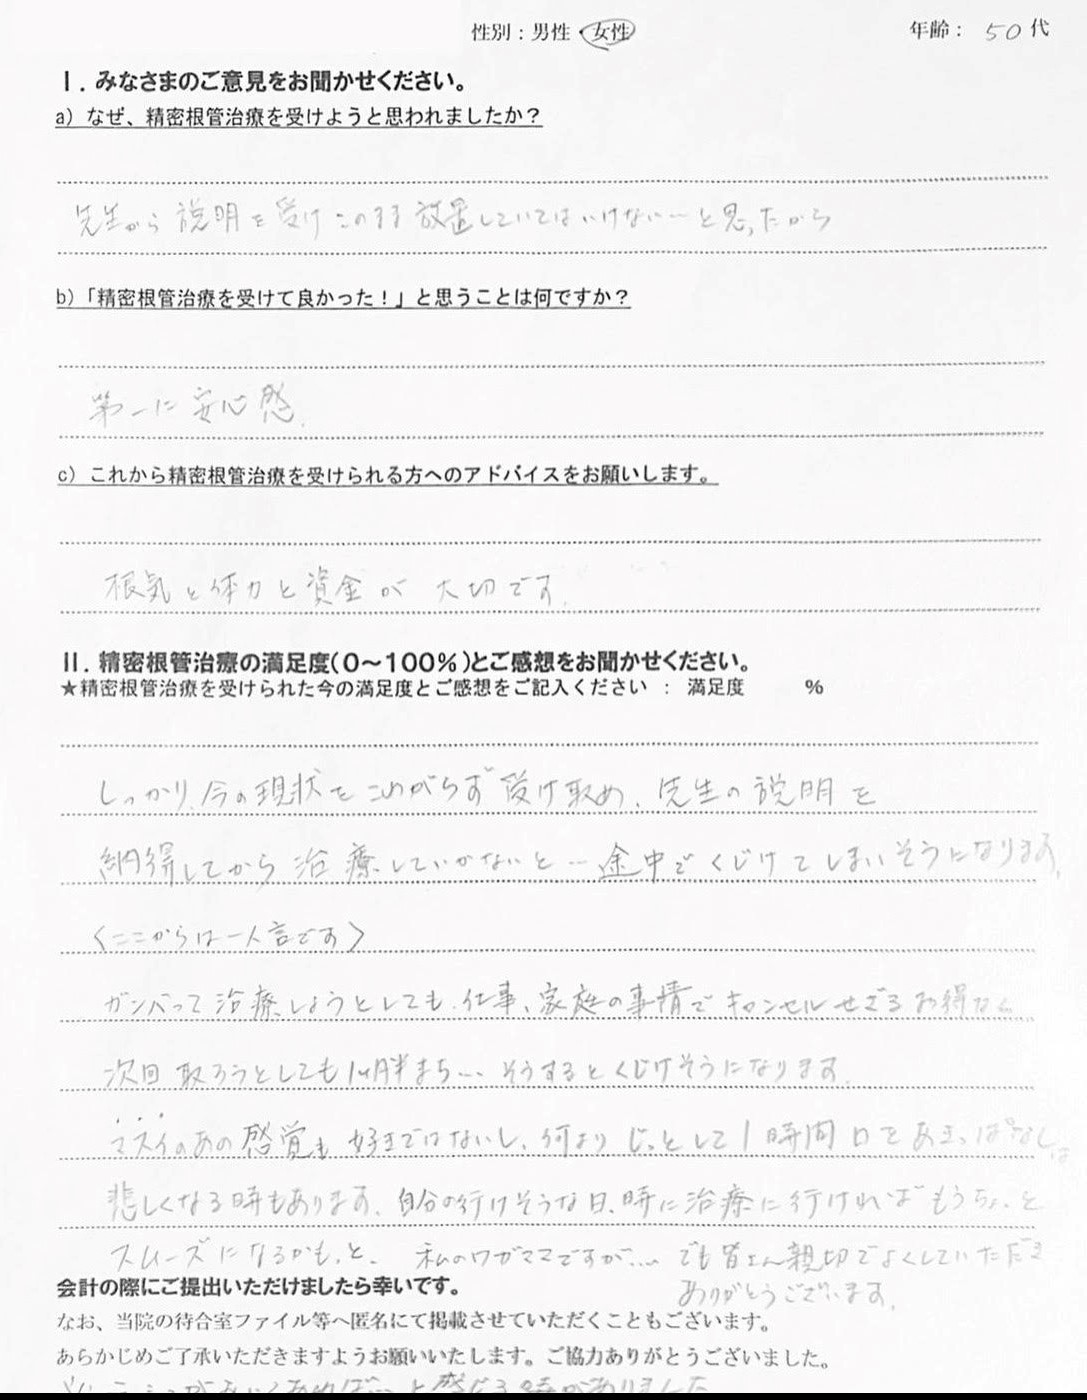

【患者様の声】精密根管治療を受けた50代女性の方です

こんにちは! 南館歯科クリニックの歯科衛生士 山崎です。 精密根管治療を受けた方の、実際の声をご紹介します。 貴重なご意見ありがとうございます😊 なかなかアポイントが合わせられず、ご不…